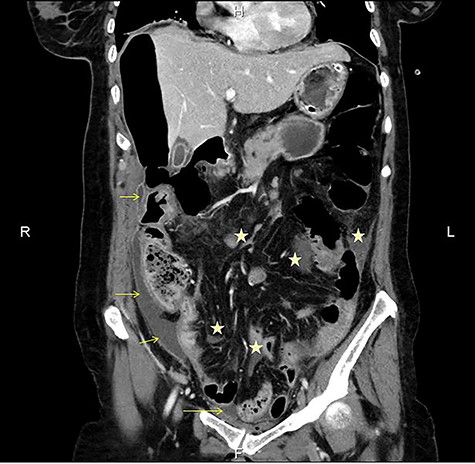

CT multiplanar reconstruction (upper level, supine position) shows free air in continuity with intraluminal (duodenum) air. Notice the presence of free fluid in mesenteric pouches (stars), as well as encapsulated in the right paracolic gutter (arrows) and Douglas space (long arrow).

Subsequently, an emergent exploratory laparotomy was decided upon. The exploration of the peritoneal cavity revealed a large amount of dirty fluid, total absence of the anterior and lateral walls of the first part of the duodenum and total bowel discontinuation after the pylorus (Fig. 4). No other disorder or sign of metastasis was present. The pylorus was sutured, a transmesocolic gastroileac anastomosis was performed and a Pezzer tube was placed in the duodenal remnant. Three drains, in Douglas, and in the right and left space were also placed. Empirical triple antibiotic treatment was administered. Postoperatively, the patient remained in the intensive care unit for 24 h. Her hospital stay was further complicated with wound dehiscence and spontaneous low-output enterocutaneous fistula, which were treated conservatively. The patient was discharged in good health on the 28th postoperative day, and the Pezzer tube was safely removed 1 week later.